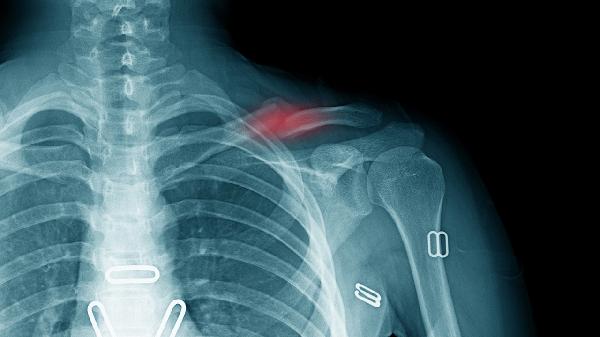

眼眶眶壁骨折多久能好 眼眶眶壁骨折的恢复方法介绍

眼眶眶壁骨折一般需要4-8周恢复,实际时间受到骨折类型、损伤程度、治疗方式、年龄因素和并发症情况等多种因素的影响。